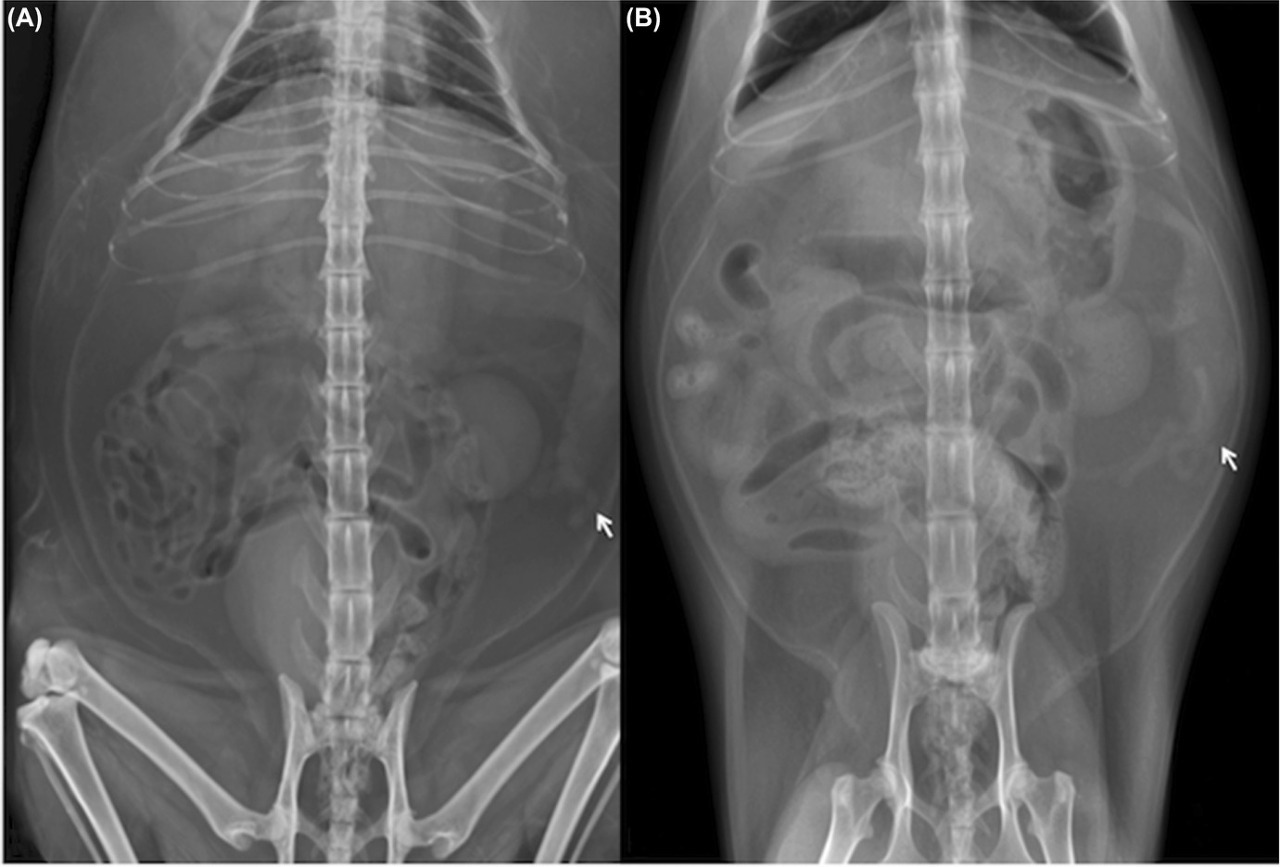

방사선 검사상의 소견은

이런 양상인데